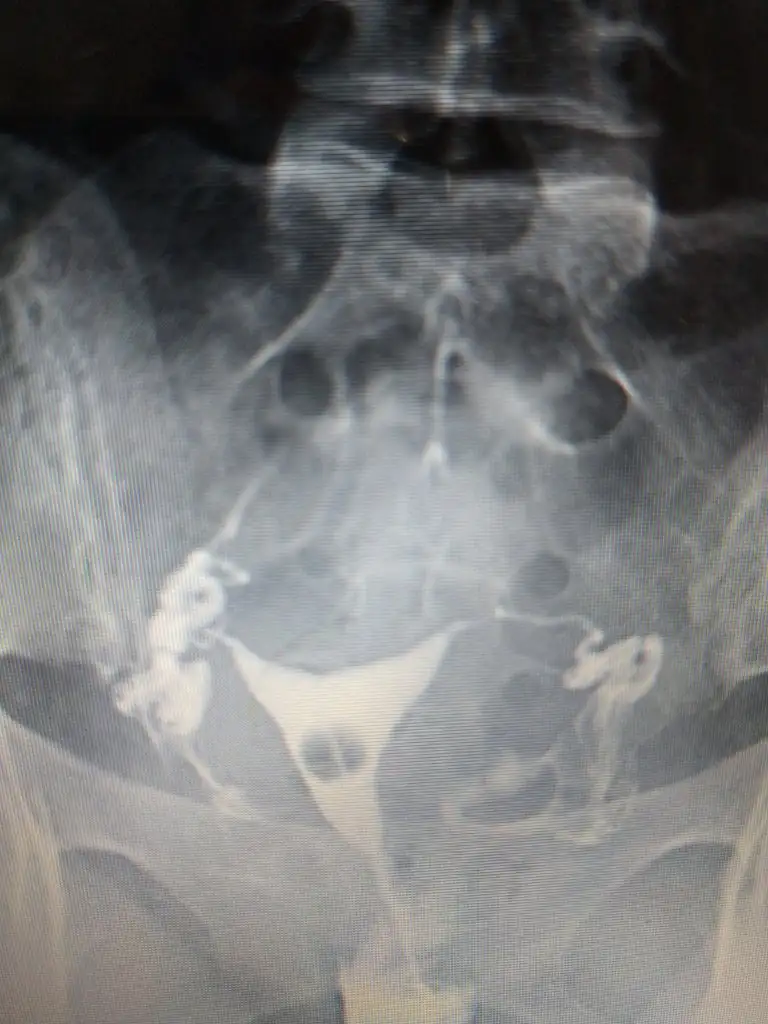

Onun hatlar karışık biraz. Çekim sonrası radyologun mesai saati bittiği için rapor yetişmemiş. Pazartesi alacak sonucunu. Kendi doktoru tüplerden birinde tıkanıklık var gibi konuşmuş ama başka doktorlara da göstermiş, basınçla açılmış demişler

pazartesi herşey sonuçlancak demek. Açılmıştır kuzum bak sorunun nerde olduğu anlaşıldı en azından en kısa zamanda gelecek beben